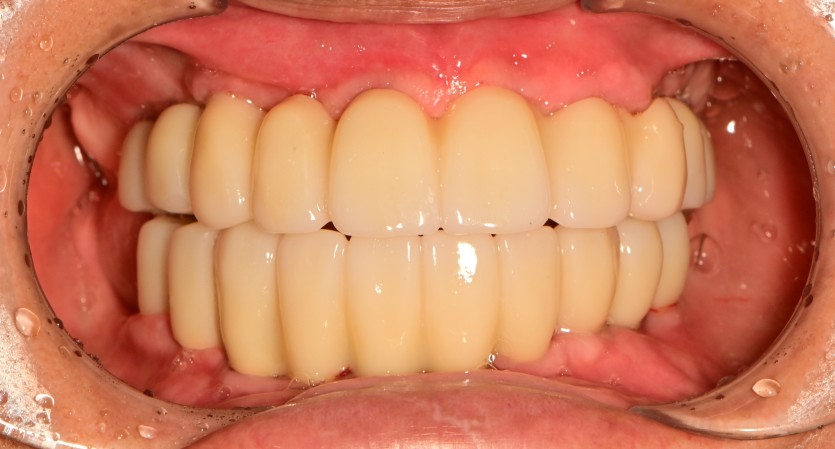

만 65세 상,하악 전체 임플란트 증례

상,하악 전체 임플란트 증례입니다.

16개의 임플란트로 완성하였습니다.